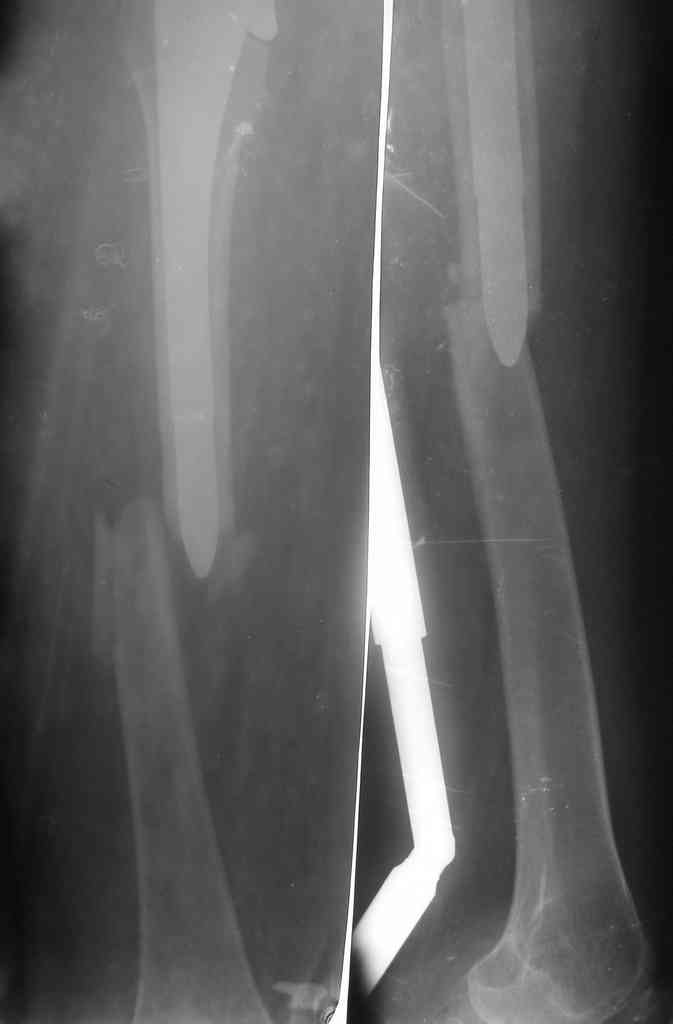

The bridging plate is a weak constuct for angular stresses and hence the deformity. The best option would be a revision THR with an open mind. After exposure one should see the integrity of the cup which is not clearly visible here. The stem is in Valgus and hence the fracture. IT needs to be revised to a long stem like the Wagner system with its 8 fins or a Proximal fit modular stem from J& J. ( both uncemented) Once again plating is not a good option against bending stresses in the femur.

Stems you show are fine but removing a well fixed AML stem means an extended trochanteric osteotomy, cutting the stem below its metaphyseal flair, then over reaming the distal piece of prosthesis. Can be done but is difficult, requires specialized equipment, and will create a lot of proximal bone loss and proximal femoral instability. Also, with the fracture, exposure of the hip joint is difficult because you can't rotate the hip by moving the lower leg. This means clamps on the proximal fragment further devascularizing the bone. You will be left with a bag of bone proximally using less than ideal distal fixation to encourage bone ingrowth to your revision prosthesis. Now you need ingrowth AND union.

Вася, привет. Честно говоря не хотел писать, но увы не увидел

ни одного предложения, позволяющего избежать повторения деформации.

Прошу прощения, но вопрос принципиальный и более глубокий, чем

покажется на первый взгляд.

Данная деформация в этой области закономерна для любой пластины при

современном подходе - угловая стабильность якобы дает пластине

свойства внутреннего фиксатора ( аналог аппарата НЧО). На практике

это не так. Сравниться по биомеханике может только и\м стержень, но

не пластина - данной постановке.

Суть вот в чем: пластина "держит" только на своей стороне - в месте

прилегания. Биомеханическая ось нагрузок бедра проходит мимо кости от

головки бедра к м\мыщелковому возвышению. Бедро испытывает сгибающие

нагрузки при опоре и если по внутреннему кортикалу нет опоры, или она

подвергается избыточной нагрузке до сращения и лизируется - это

усугубляет деформацию. Таким образом пластину выгоднее ставить с

внутренней поверхности бедра, чтобы она могла более менее

противостоять этой нагрузке (стержень может - это понятно). При